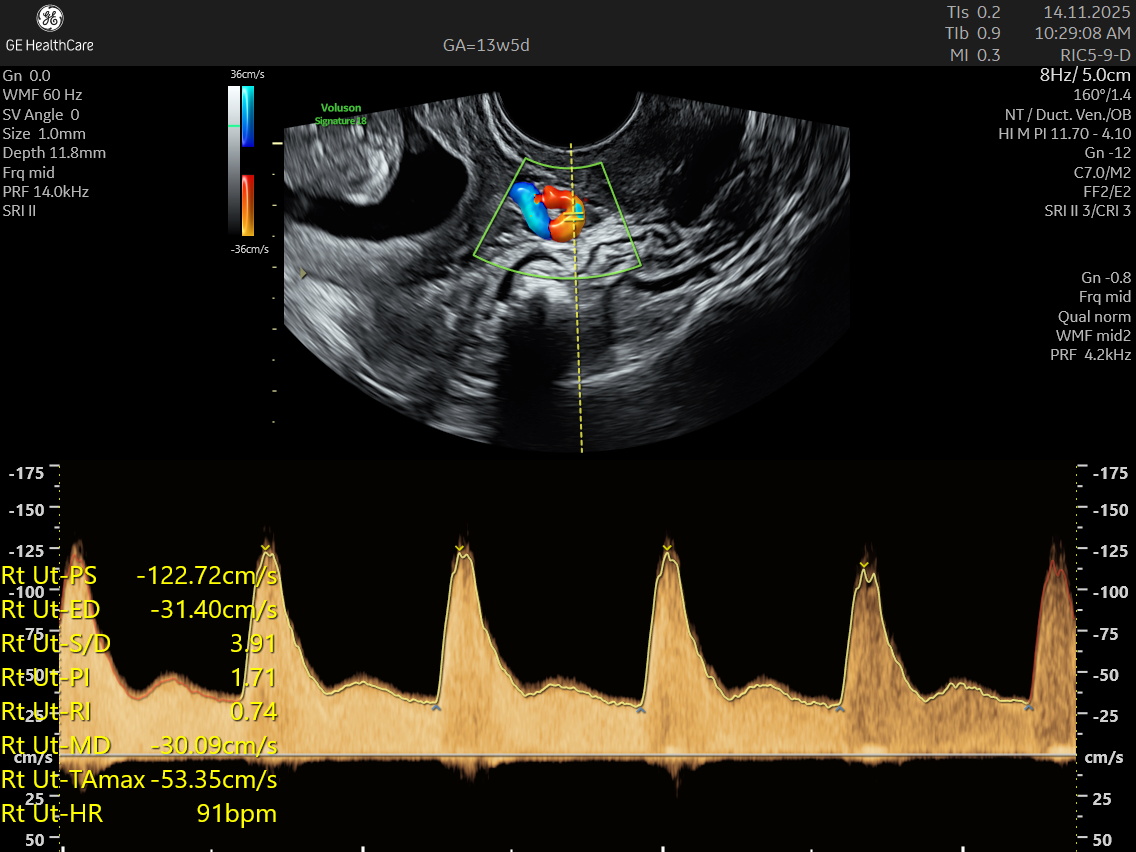

NESA Institute of Fetal Medicine offers specialized first-trimester screening for expectant parents, delivering high-precision NT scans between 12 to 13 weeks of pregnancy. Our experienced fetal medicine team ensures accurate risk assessment for chromosomal abnormalities, including Down syndrome, Edwards syndrome, and Patau syndrome.

The NT scan is a non-invasive ultrasound examination conducted in the first trimester (12–13 weeks). It measures the nuchal translucency (the fluid at the back of the fetus’s neck) and combines it with the maternal blood test for a detailed risk profile. NT Scan is an important early screening test for Down syndrome (Trisomy 21), Edwards syndrome (Trisomy 18), and Patau syndrome (Trisomy 13).

Although the NT scan is mainly a screening tool and not diagnostic on its own, it can identify about 50% of major fetal abnormalities when combined with other assessments like blood tests and detailed ultrasound. The scan also helps to screen some basic anatomical structures during the first trimester, especially the fetal heart anatomy, brain, face, spine, stomach, abdominal wall, kidneys, bladder, and extremities to varying degrees depending on gestational age and maternal factors.